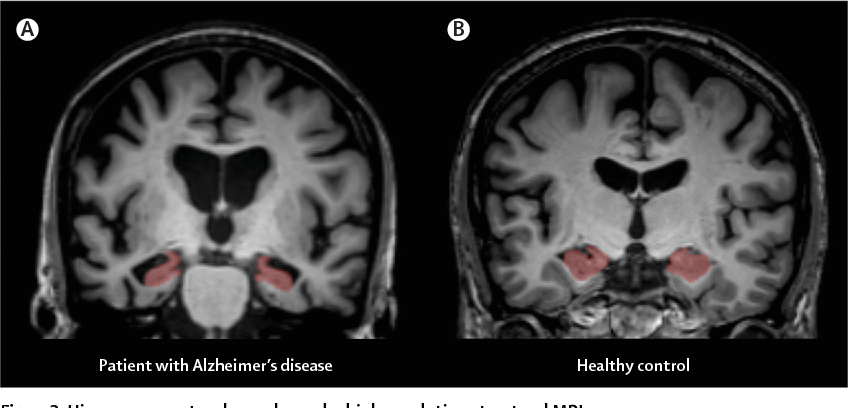

Dying cells cause brain shrinkage

Allows for measurement of the 3-dimensional (3D) volume of brain structures, especially the size of the hippocampus and ventricles enlargement